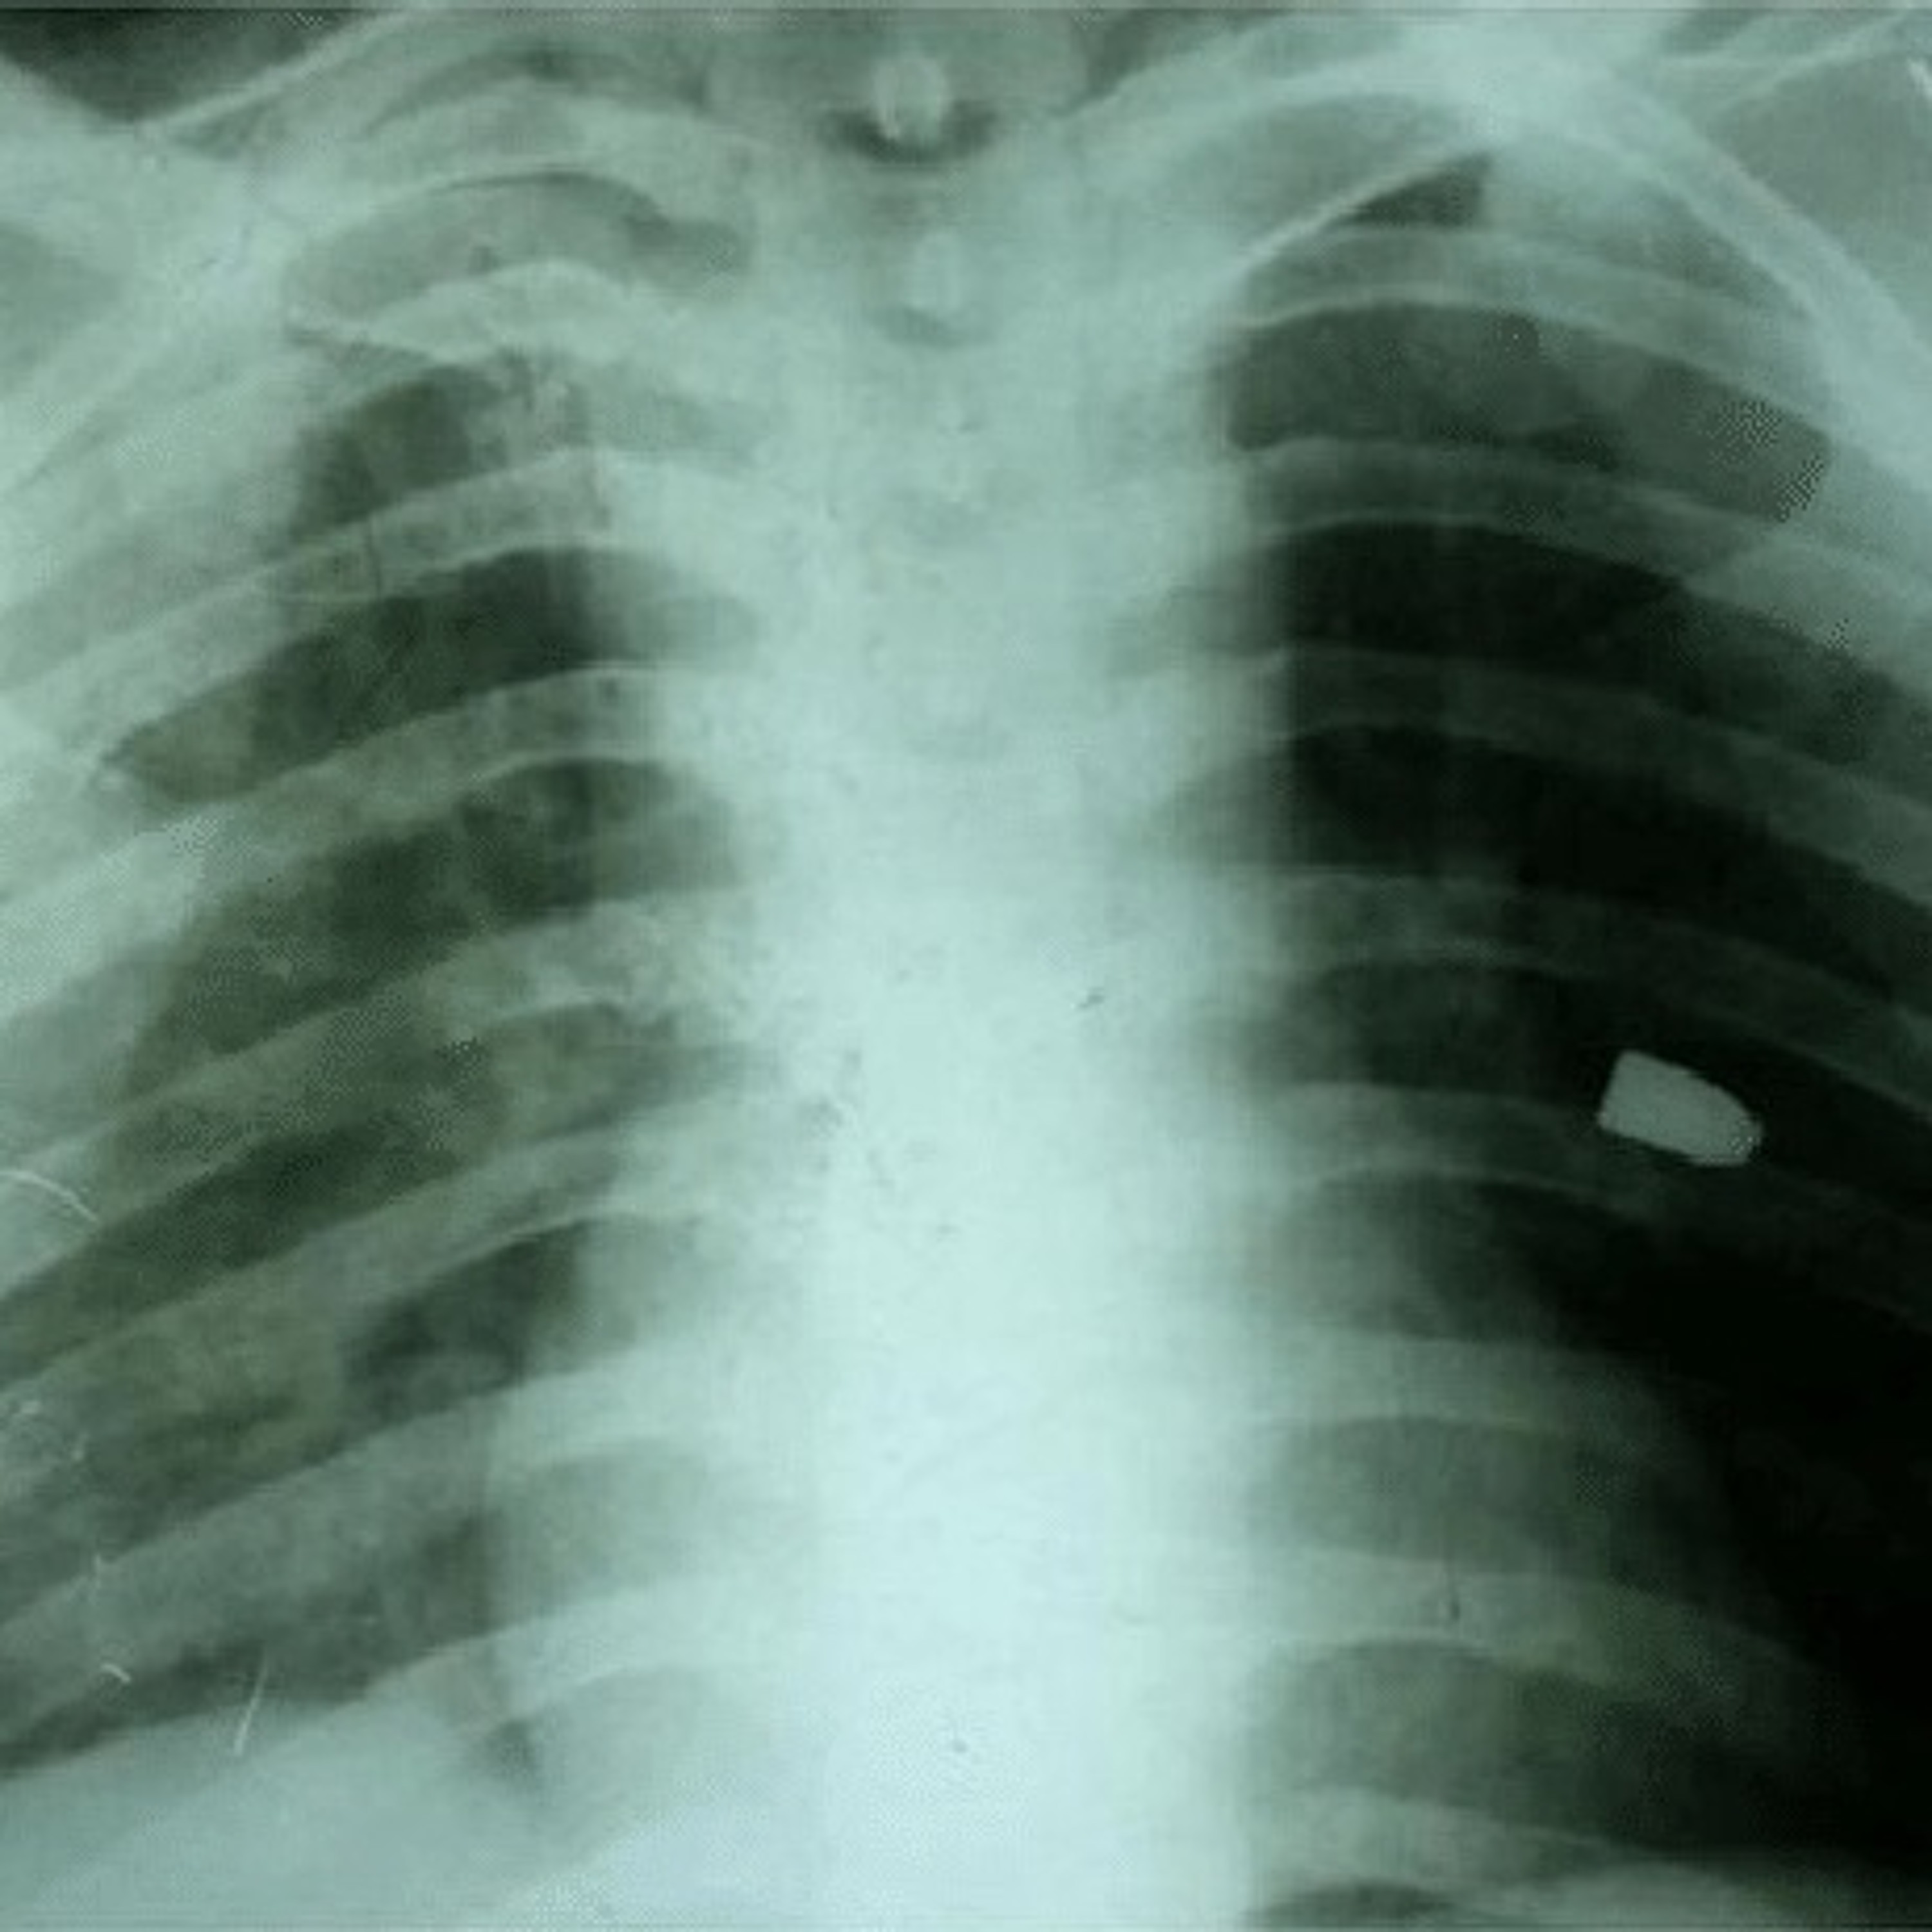

Gunshot wounds (GSWs) come in many flavors and those to the chest can be particularly dicey. Yet, a chest GSW can be a minor flesh wound, a major traumatic event with significant damage, or deadly. If you have a character who suffers such an injury, this podcast is for you.